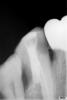

Inspiration Опубликовано 3 июля, 2009 Поделиться Опубликовано 3 июля, 2009 снимок бы другой,с верхушкой,и вообще полностью корень чтобы видно было Ссылка на комментарий

Rania Опубликовано 3 июля, 2009 Автор Поделиться Опубликовано 3 июля, 2009 снимок бы другой,с верхушкой,и вообще полностью корень чтобы видно былопосмотрите пожалуйста, бифуркация не продырявлена, Ссылка на комментарий

Scrabble Опубликовано 3 июля, 2009 Поделиться Опубликовано 3 июля, 2009 (изменено) посмотрите пожалуйста, бифуркация не продырявлена,Чтобы быть уверенным-снимков должно быть несколько. В разных проекциях. А тут ничего не скажешь. Антибиотики при "болях по переходной"-это из пушки по воробьям. ИМХО. Изменено 3 июля, 2009 пользователем Scrabble Ссылка на комментарий

dantistSergo Опубликовано 6 июля, 2009 Поделиться Опубликовано 6 июля, 2009 (изменено) http://s60.radikal.ru/i170/0907/53/c716bc63b146.jpgПохоже, что перфорации нет, стоит в небном пустом канале (сужу по параллельности с видимым участком небного 6). Боли по переходке от обострения. В медиальном щечном - 2 канала. Изменено 6 июля, 2009 пользователем dantistSergo Ссылка на комментарий